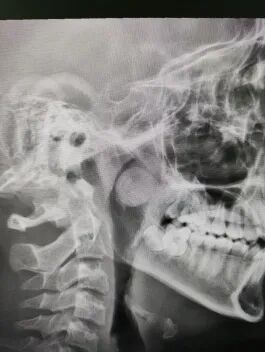

耳鼻喉科接诊医生查体发现,可可的鼻塞不伴随打喷嚏和流鼻涕。进一步详细检查,结果显示,可可的左侧鼻腔后端有一处直径近2厘米的肿物。肿物不仅堵塞了后鼻孔及鼻咽部,还阻碍了鼻窦的引流,引起了鼻窦炎。

术后的病理检测结果显示切除的肿物为良性(鼻息肉)。家长悬着的心终于放下了。

鼻息肉是一种常见的鼻部慢性疾病,外观上像新鲜荔枝,表现为一个或多个表面光滑、触之柔软、半透明的肿物,可以出现在鼻腔和鼻窦黏膜的任何部位。鼻息肉常表现为持续性鼻塞并呈进行性加重,甚至完全阻塞鼻腔通气,鼻塞严重者表现为闭塞性鼻音、睡眠打鼾、分泌物增多、嗅觉减退或丧失。一旦治疗不及时,就会导致病情加重,鼻息肉越长越大,直至填满整个鼻腔,最终导致鼻子变形,鼻背变宽,形成了外观酷似青蛙的鼻子——“蛙鼻”。